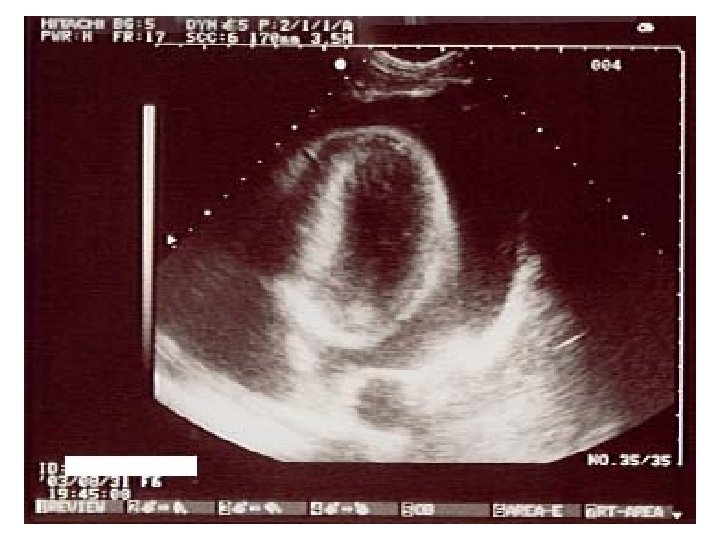

Ultrasound imaging: carotid artery • This is also a carotid artery. • The flow is not all in the same direction. It is turbulent, like rapids in a river. • This is usually due to a build-up of fatty deposits in the artery